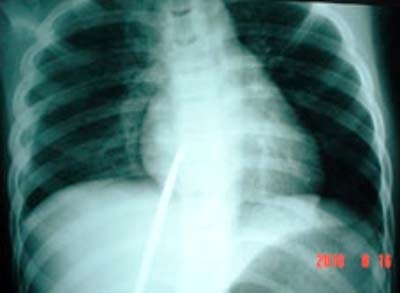

Cây chỉa đâm thủng màng phổi phải và xuyên tâm thất phải

Theo ghi nhận của bác sĩ, khi mới nhập viện T. tỉnh táo, mạch và huyết áp ổn, nhưng đau nhiều, khó thở. Thanh kim loại đâm chéo từ vùng thượng vị bên phải chếch lên trên và sang trái. Đoạn ngoài thành ngực chừng 7cm đang di động theo nhịp đập của tim. Trên phim X quang cho thấy thanh kim loại đâm vào thất phải theo hướng chếch từ dưới lên.